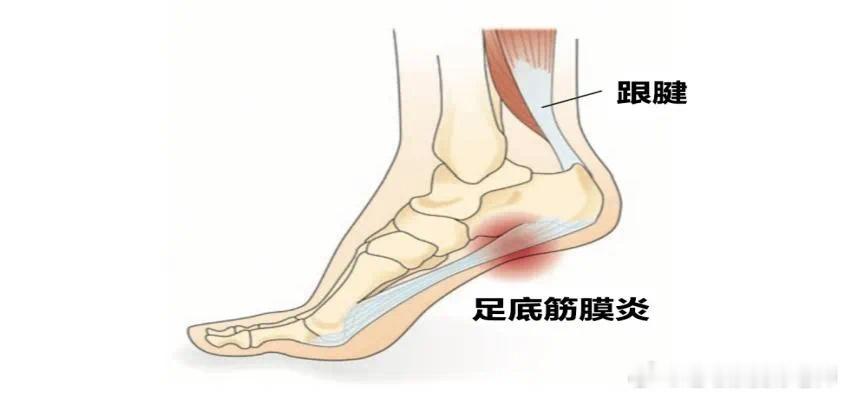

【足底筋膜炎原因】①小腿三头肌和跟腱的过度使用——我们小腿三头肌移形成跟腱,跟腱跨过跟骨和足底筋膜是移形存在的,所以张力也是共通的。

很多朋友喜欢踮着脚走路,或运动时用小腿去发力,那如果小腿过度紧张,足底筋膜的张力也会很高,导致疼痛。

②下肢力线不正——很多人的足底筋膜疼痛,更多是脚内侧疼痛,很多人的踝关节是外翻的,足弓是塌陷的,在这种情况下,脚的内侧会承受一个更大的身体压力,内侧足底筋膜被牵拉,导致慢性损伤的疼痛。